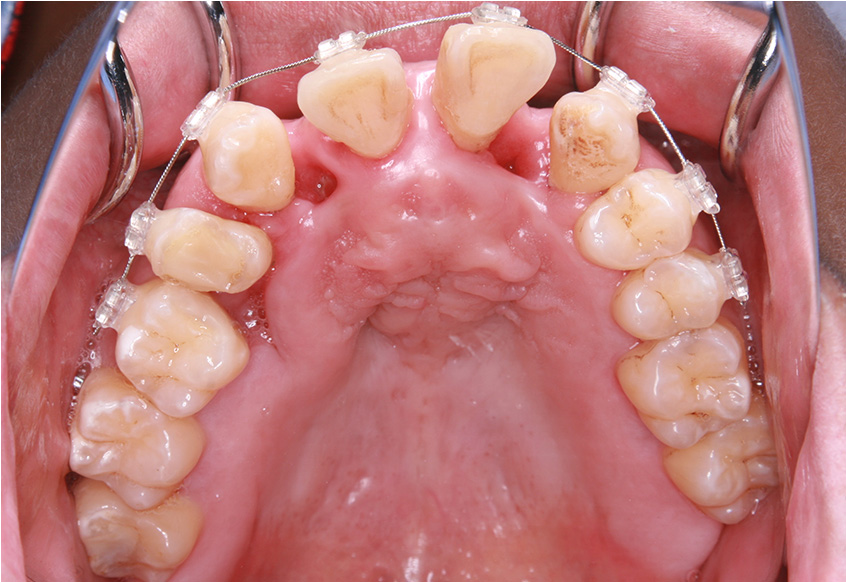

最初のお口の中 ワイヤー装着して治療を開始

-

6ヵ月経過すると、矯正治療を終了し、前歯に被せ物の治療を行いました。

最初のお口の中 2025/3/22

被せ物装着

| 治療内容 | 上顎側切歯を2本抜歯した後、上顎の歯にブラケットを装着し、ワイヤー、矯正用ゴムで歯の移動を行いました。その後、被せ物の治療を行って治療を終了しています。 |